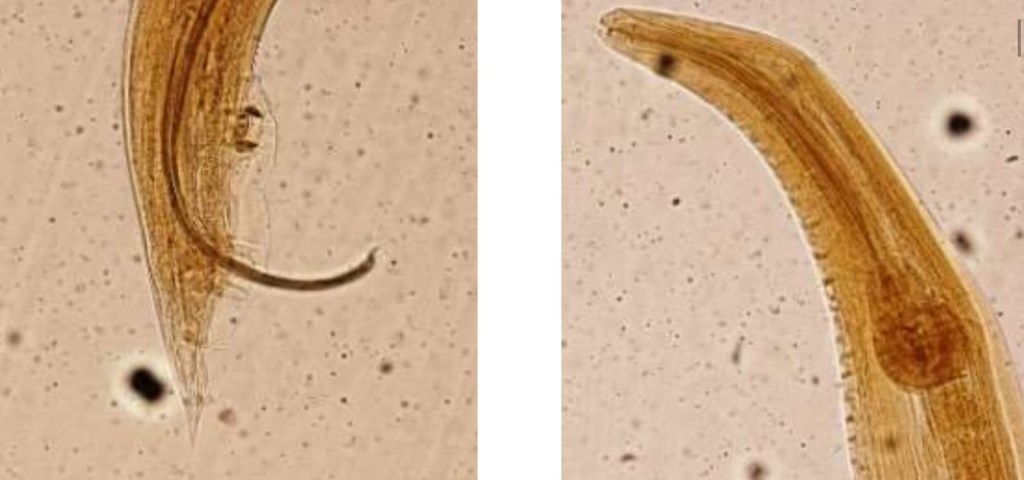

Heterakis gallinarum, dünya çapında birçok evcil ve yabani kuşun (Galliformes takımı) kör bağırsağında bulunur. Erkekleri 6-13 mm, dişiler ise 9-15 mm uzunluğundadır. Anterior kısımda bulunan oesophagusun posterior kısmında bulbular genişleme bulunur. Yetişkin parazitler uzun yan kanatlara sahiptir. Posterior kısım dişilerde düz sonlanır, vulvar açıklık orta kısımdadır . Erkeklerde ayrıca kuyruk kanatları ve kloaka öncesi bir çekmen bulunur. Yumurtaları 65-80 × 35-45 µm boyutlarında, koyu renkli, kalın kabuklu ve pürüzsüzdür.

(USAMV Cluj-Napoca, Veteriner Fakültesi, Parazitioloji Anabilim Dalı Arşivi)